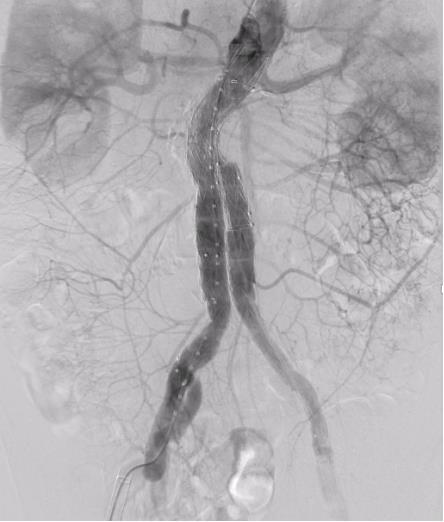

图7 术后造影无内漏Fig.7 Completion angiography shows no endoleak